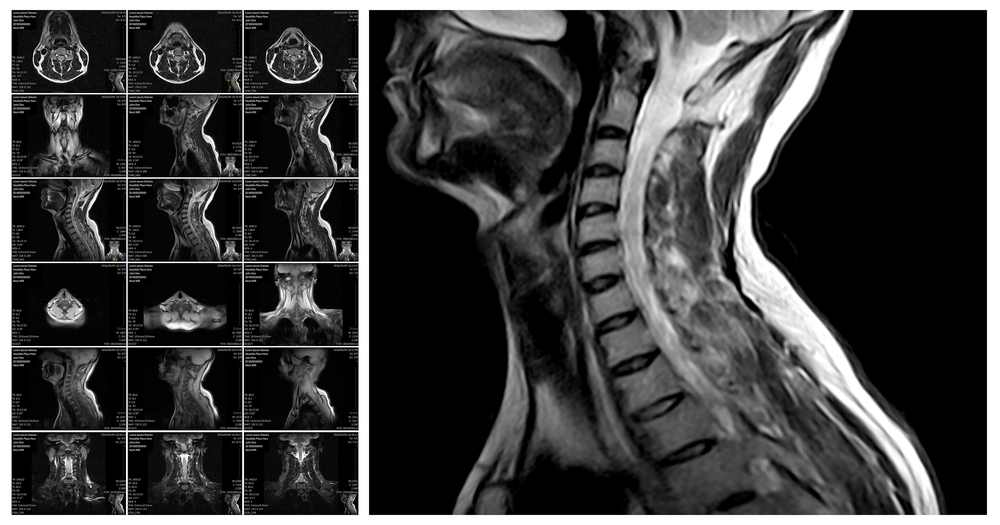

Диагностика

- КТ, МРТ.